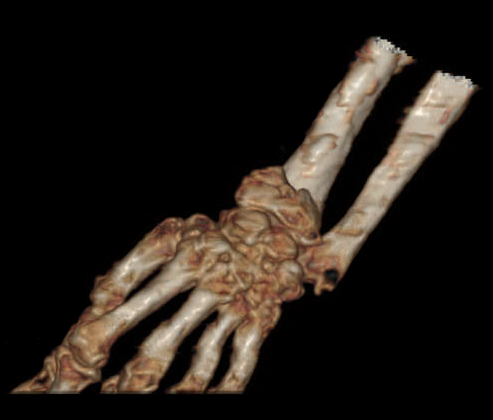

术前腕关节CT

2、左桡骨远端骨折